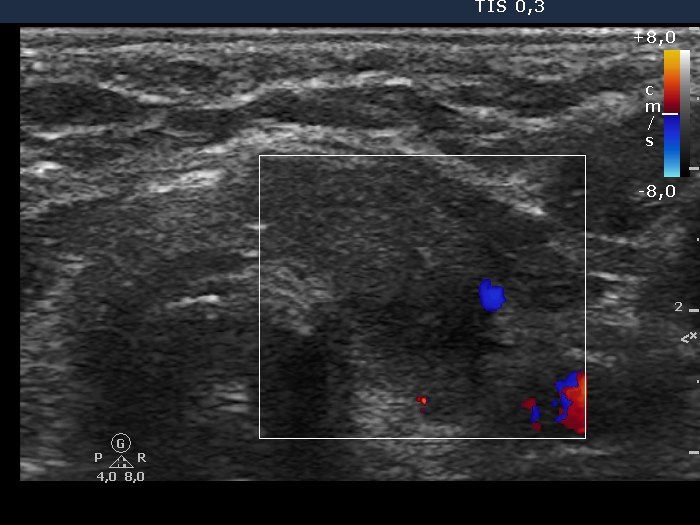

Subacute granulomatous de Quervain's thyroiditis - Case 10. (ultrasonographic picture 6)

Left lobe, horizontal view, color Doppler mode. The vascularization is decreased.